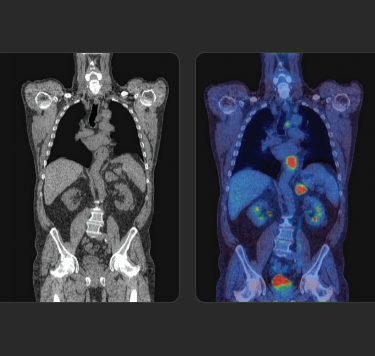

Tratar o que se vê

Os radioligandos podem ter uma finalidade e aplicação diagnóstica e terapêutica, permitindo uma abordagem teranóstica, que pode ser traduzida pela afirmação "tratar o que se vê e ver o se trata" (do inglês "see what you treat and treat what you see"). 1b 4 5

A ciência

RLT representa uma evolução em direção ao tratamento de precisão

RLT é uma abordagem de medicina de precisão que reconhece e trata diretamente a doença, com um foco particular nos cancros avançados.

Recorrendo ao poder dos átomos radioativos, RLT é capaz de dirigir radiação às células-alvo em qualquer parte do corpo.7a 8a